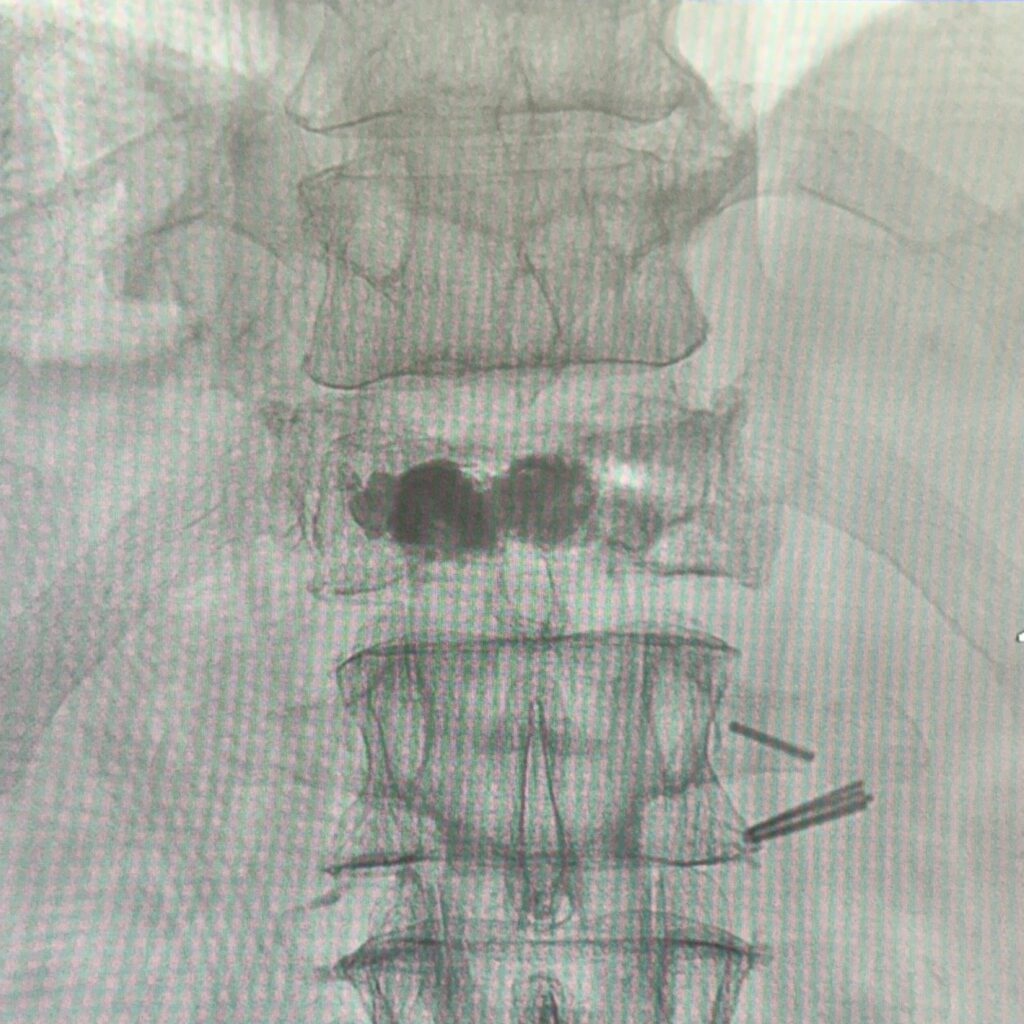

Figura 4: Imagine statică în plan sagital din angiografie pentru verificarea distribuției cimentului de vertebroplastie

Figura 5: Imagine statică în plan coronal din angiografie pentru verificarea distribuției cimentului de vertebroplastie

Se practică kifoplastie unipediculara cu balon.

Rezultat optim postprocedural: remiterea cvasicompletă a durerilor vertebrale.